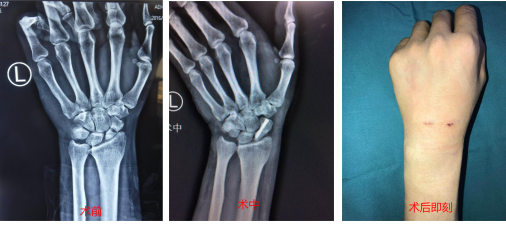

一年前骑车摔倒,左手腕舟骨骨折一年多未愈合,腕关节镜下植骨治疗后恢复。

手外二齐伟亚主任做关节镜下植骨固定术